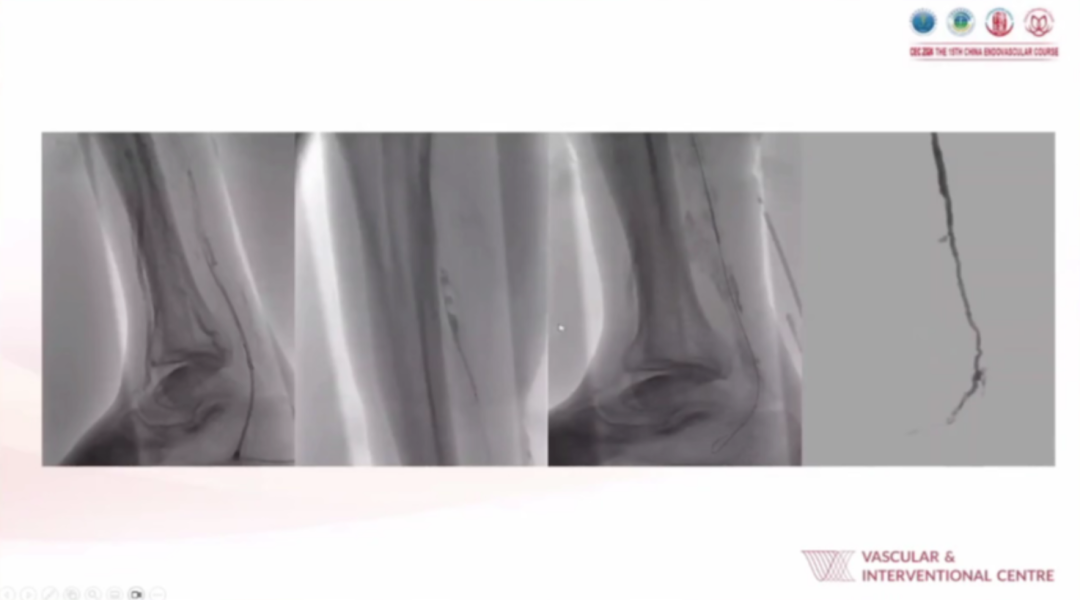

手术实施时,麻醉方式以静脉镇静或局部麻醉为主(仅大范围伤口清创时选用全麻);入路策略优先选择桡动脉处理髂动脉、股浅动脉(SFA)病变,顺行入路为首选;技术上借助CO₂造影、SMART Perfusion技术实时评估血流,配合积极的抗血小板治疗,还会灵活运用Auryon激光斑块切除术、改良深静脉动脉化等手段应对复杂病变。

从典型病例影像(包括常规CLTI病例、需激光斑块切除联合支架植入的病例、改良深静脉动脉化病例等)可见,术后通过血管造影、血流灌注成像等能清晰看到病变血管的血流恢复情况,验证了日间手术策略在CLTI肢体挽救中的有效性。

针对难治性CLTI病例,该患者尝试“血管成形术+股-胫前动脉旁路术”均未成功,肢体存在严重坏死、感染伤口,最后临床采用积极血运重建,展示恢复肢体血流的操作,通过介入等手段打通闭塞血管,为后续伤口愈合创造条件。